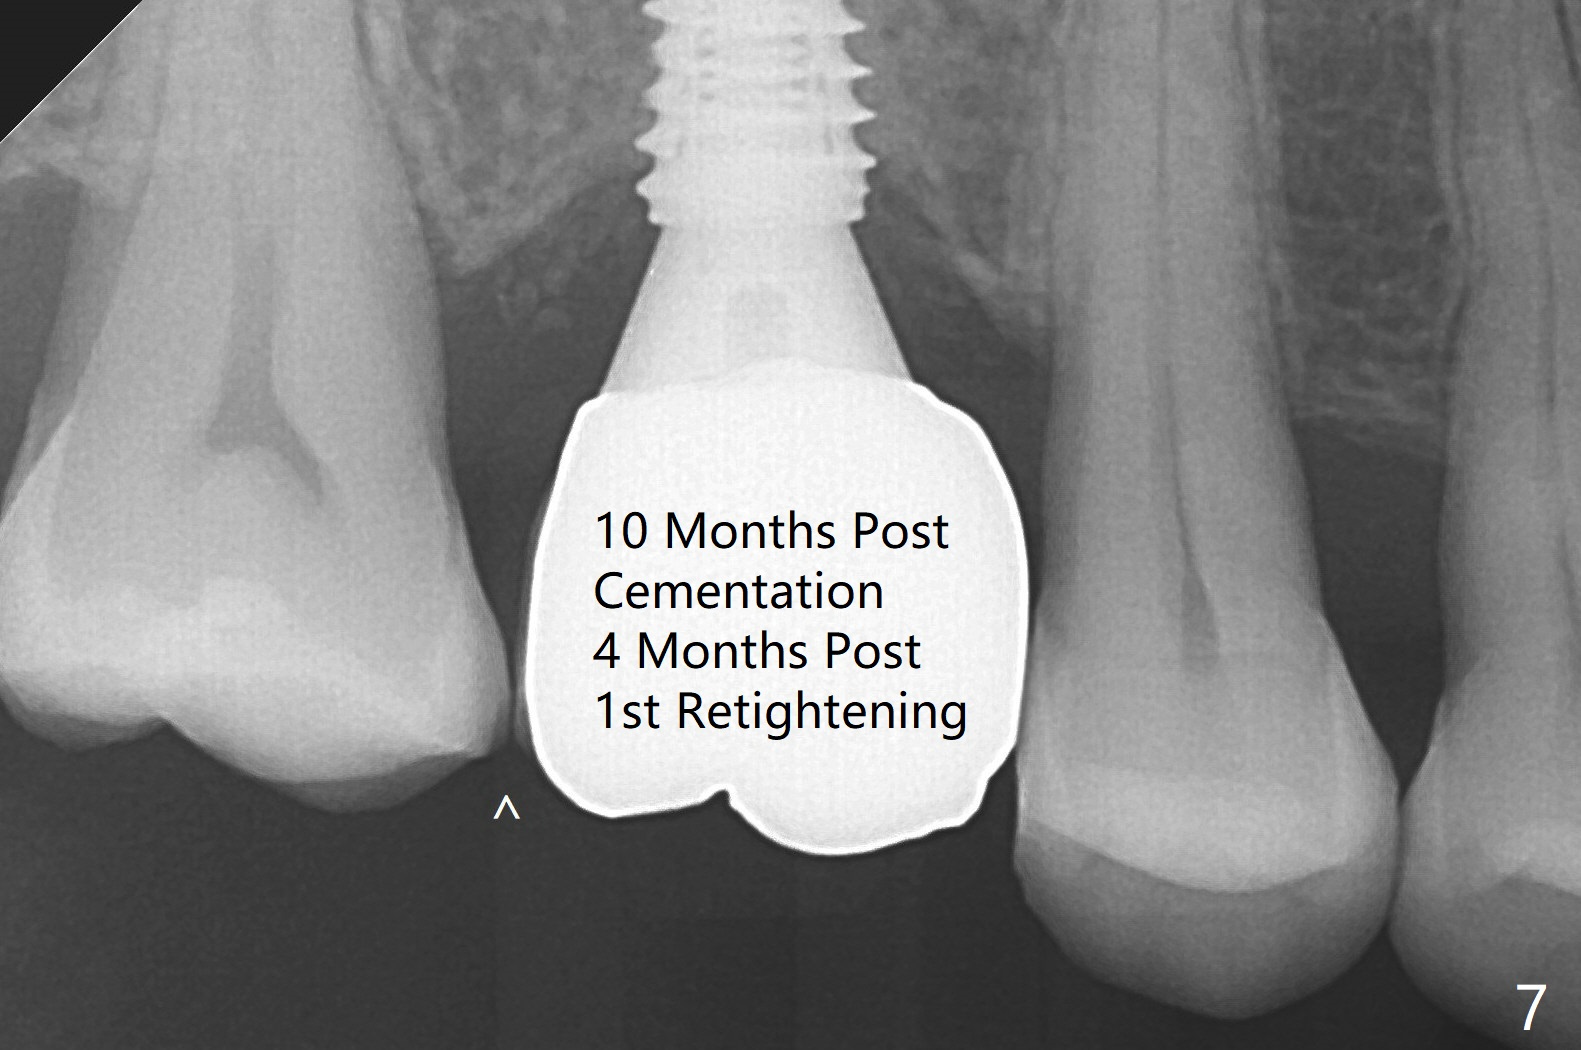

With understanding tissue punch and engagement of drill as much as possible into guide sleeve before pressing pedal, guided surgery is accomplished with confidence (Fig.1,2).  With undersized drilling, there is no thread exposure palatally, when a flap is raised.  Vanilla graft is placed, since it has been prepared before incision.  No membrane is used.  It appears that the palatal bone expands while the implant is being placed.  CBCT taken 10 days postop shows apparently the coronal end of the palatal plate (Fig.3 arrows) and bone graft (<).  Although postop pain is slightly more associated with incision for bone graft, the wound heals with periodontal dressing 10 days postop.